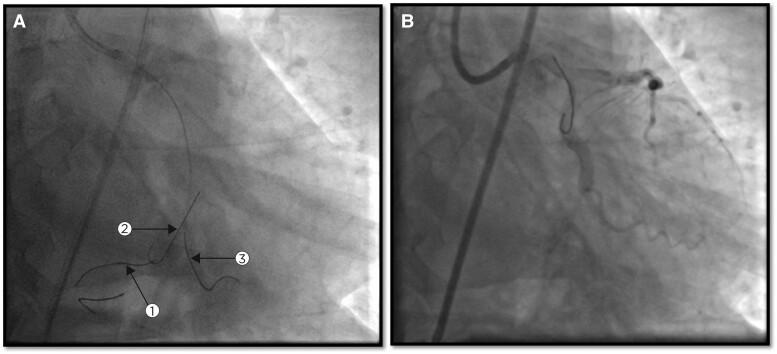

A 52-year-old male patient with diabetes and dyslipidaemia presented with posterior wall myocardial infarction. An angiogram revealed occlusion in the left circumflex (LCX) artery. Attempts to pass a guidewire through the lesion led to its entrapment and eventual fracture. Several techniques and manoeuvres failed to retrieve the fractured guidewire, which remained lodged in the LCX. An endovascular snare catheter also proved unsuccessful. The fragment was eventually removed using the triple-wire technique, although this caused coronary perforation and dissection. The perforation was identified and stented. A subsequent stent addressed a dissection in the left main/left ascending artery area, likely caused by the coronary snare. These interventions were crucial in stabilizing the patient's condition, leading to recovery with a left ventricular ejection fraction of 50% and a viable LCX artery. The patient exhibited an uneventful progression at the 1-year follow-up.

一名52岁男性患者,患有糖尿病和血脂异常,出现后壁心肌梗死。血管造影显示左旋支(LCX)动脉闭塞。试图使导丝穿过病变部位导致导丝陷入并最终断裂。多种技术和操作未能取出断裂的导丝,其仍留在LCX中。血管内圈套导管也未成功。最终采用三线技术取出了碎片,尽管这导致了冠状动脉穿孔和夹层。穿孔被识别并置入了支架。随后的支架处理了左主干/左前降支动脉区域的夹层,可能是由冠状动脉圈套器所致。这些干预措施对稳定患者病情至关重要,患者得以康复,左心室射血分数为50%,LCX动脉存活。患者在1年随访中病情进展顺利。